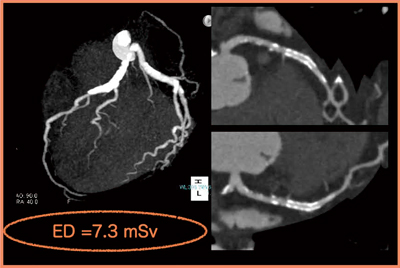

・症例3:60歳代,男性。LADにステント留置の既往があり,フォロー中に非特異的な胸痛を訴えた。

不整脈があるため,100kV,R-R 30〜80%とし,念のために2beat scanして,得られたデータから最適な画像を取得することとした。LADの近位部から中間部にかけ,ステントとともに強い石灰化が描出されたものの,高速スキャンと安定した画像のcurved MPRで,ステント内腔には有意狭窄がないことを確認できた(図4)。実効線量は7.3mSvだが,64列CTによるヘリカルスキャンと比較すると,かなり少ない被ばく線量で確実に検査を行うことができた。

図4 症例3:curved MPR像によるステント内腔の評価